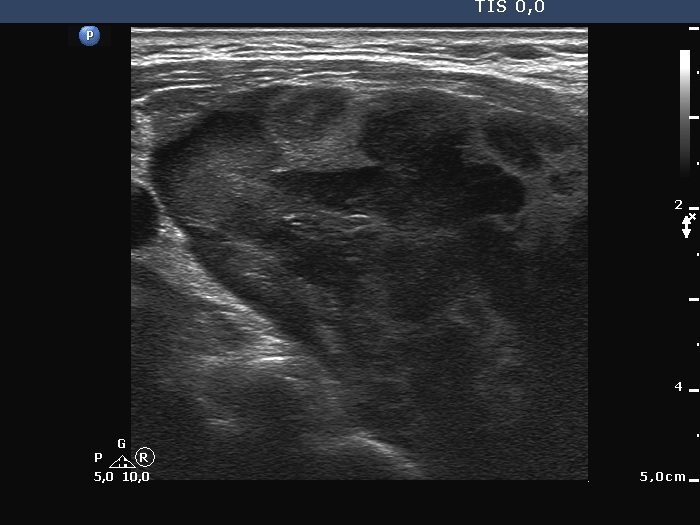

Ultrasonography. The right lobe was extremely enlarged with the dimensions of 50, 50 and 85 mm, depth, width and length, respectively. This lobe was composed of multiple hypoechoic areas within an echonormal background. The left lobe also had a hypoechoic lesion.